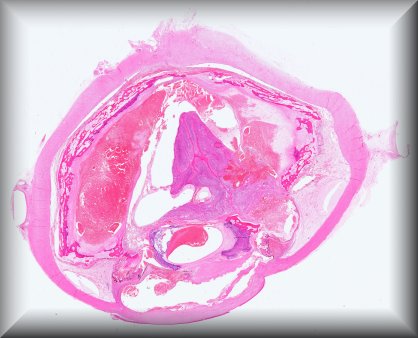

Luis Alfaro (Valencia): Rapidly growing tumour in a 51-year-old male affecting the orbit and involving the eyeball. Extended exanteration was performed, towards the skull and left facial region. Protocol |